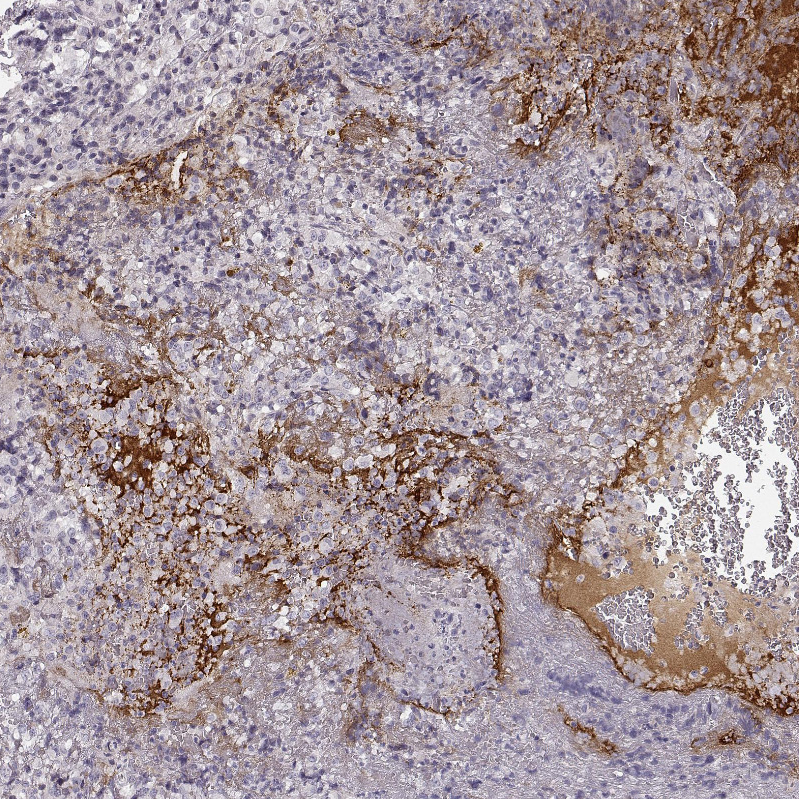

Immunohistochemical staining of human pituitary gland shows moderate cytoplasmic positivity in anterior pituitary gland.